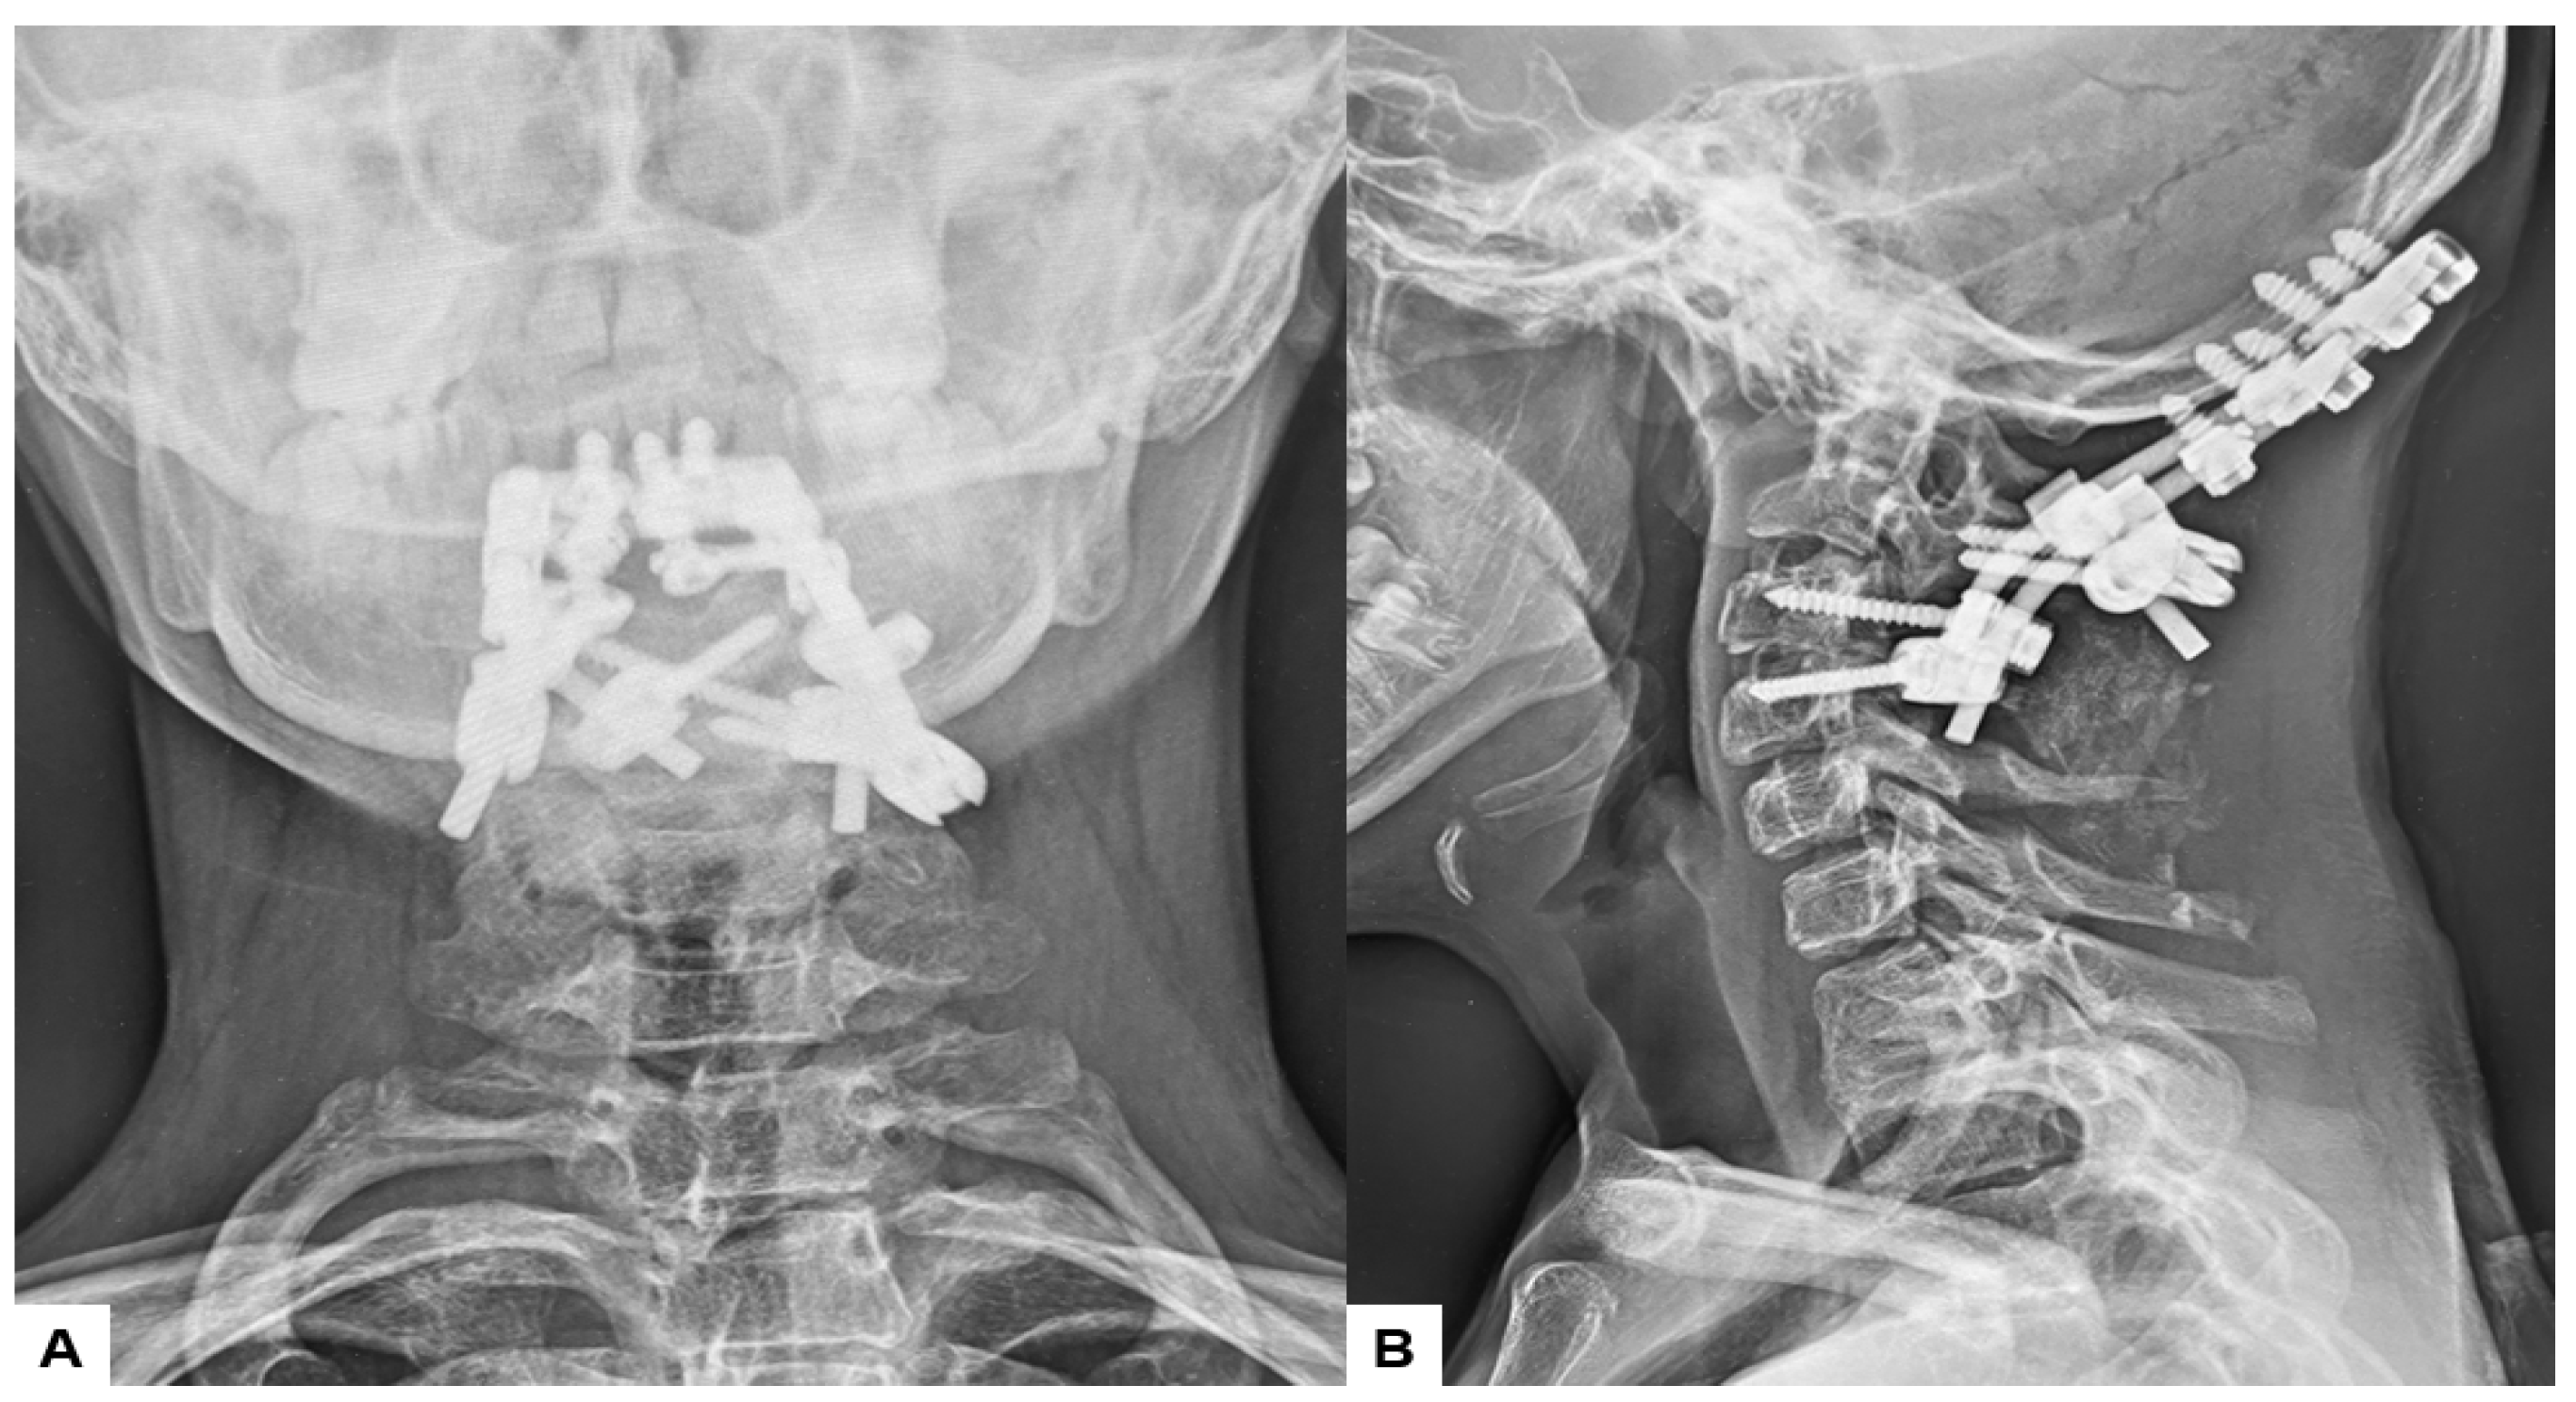

Postoperative radiographs and CT scans demonstrated successful reduction, realignment, and appropriate screw positioning. The tip of the dens now measured 6.3 mm above McGregor’s line and 2.5 mm below McRae’s line, with the cervicomedullary angle (CMA) measuring 130 degrees. Additionally, the anteroposterior (AP) diameter of the foramen magnum increased to 19.3 mm (Figure 13 and Figure 14).

Figure 13.

Postoperative radiograms, (A) Anteroposterior l radiogram, (B) Lateral radiogram.

Figure 14.

Postoperative CT. (A) Mid-sagittal reconstruction CT, (B) Coronal reconstruction CT, (C) Axial CT at C1/2, (D) Axial CT at C2/3.

Surgically, the patient was successfully treated, with a surgical time of 139 min and an estimated blood loss of 180 mL. During the one-year follow-up, manual muscle testing results and sensory function tests indicated almost full recovery in both bilateral arms (MMT 5). The patient is now walking smoothly without any gait disturbance, and the cervical Japanese Orthopedic Association score improved from 9/17 to 16/17. Postoperative radiographs demonstrated excellent spinal cord decompression, with no loss of reduction or malalignment. The cervicomedullary angle (CMA) postoperatively measured 130 degrees. Furthermore, there were no major or severe complications reported.